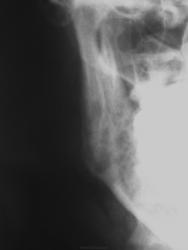

Женьщина около 30 лет,обратилась в травмпункт по поводу травмы головы (побили), на рентгенограмме выявлены изменения в углу нижней челюсти справа, была доснята челюсть (снимок который представлен) изменения на том же месте, что за изменения?

Да дама "наш клиент" хотя и выглядит прилично. При пальпации в области угла челюсти определяется крепитация, не костная, а воздушная и если присмотрется на втором представленном изображении в мягких тканях определяется просветления, а изменения в кости похоже на скиалогический феномен скрадывания, на боковой рентгенограмме изменений в углу челюсти не видно. Главный вопрос откуда воздух?

Если с костью все неплохо, то должен быть из мягких тканей. Рядышком и чуть ниже - глотка (в широком смысле). Травма в полости рта с таким объёмом газа представляется маловероятной - тогда должна быть и клиника воспаления (при ротовой-то инфекции, разве что ежедневные промывания спиртосодержащими препаратами смажут клинику).

Перелома и я не вижу, но интересна перестройка костной структуры нижней челюсти справа. А боковой предпочтительнее на мой взгляд сделать под углом, лежа, чтобы правая ветвь не наслаивалась на левую.

Ничего не увидел, на боковой нет линии перелома. Может быть не ту сторону сделали?

Если-бы не такой анамнез , первая мысль - про фиброзную дисплазию .

В боковой проекции костная ткань целая. Скорее просветления результат воздушной крепитации.